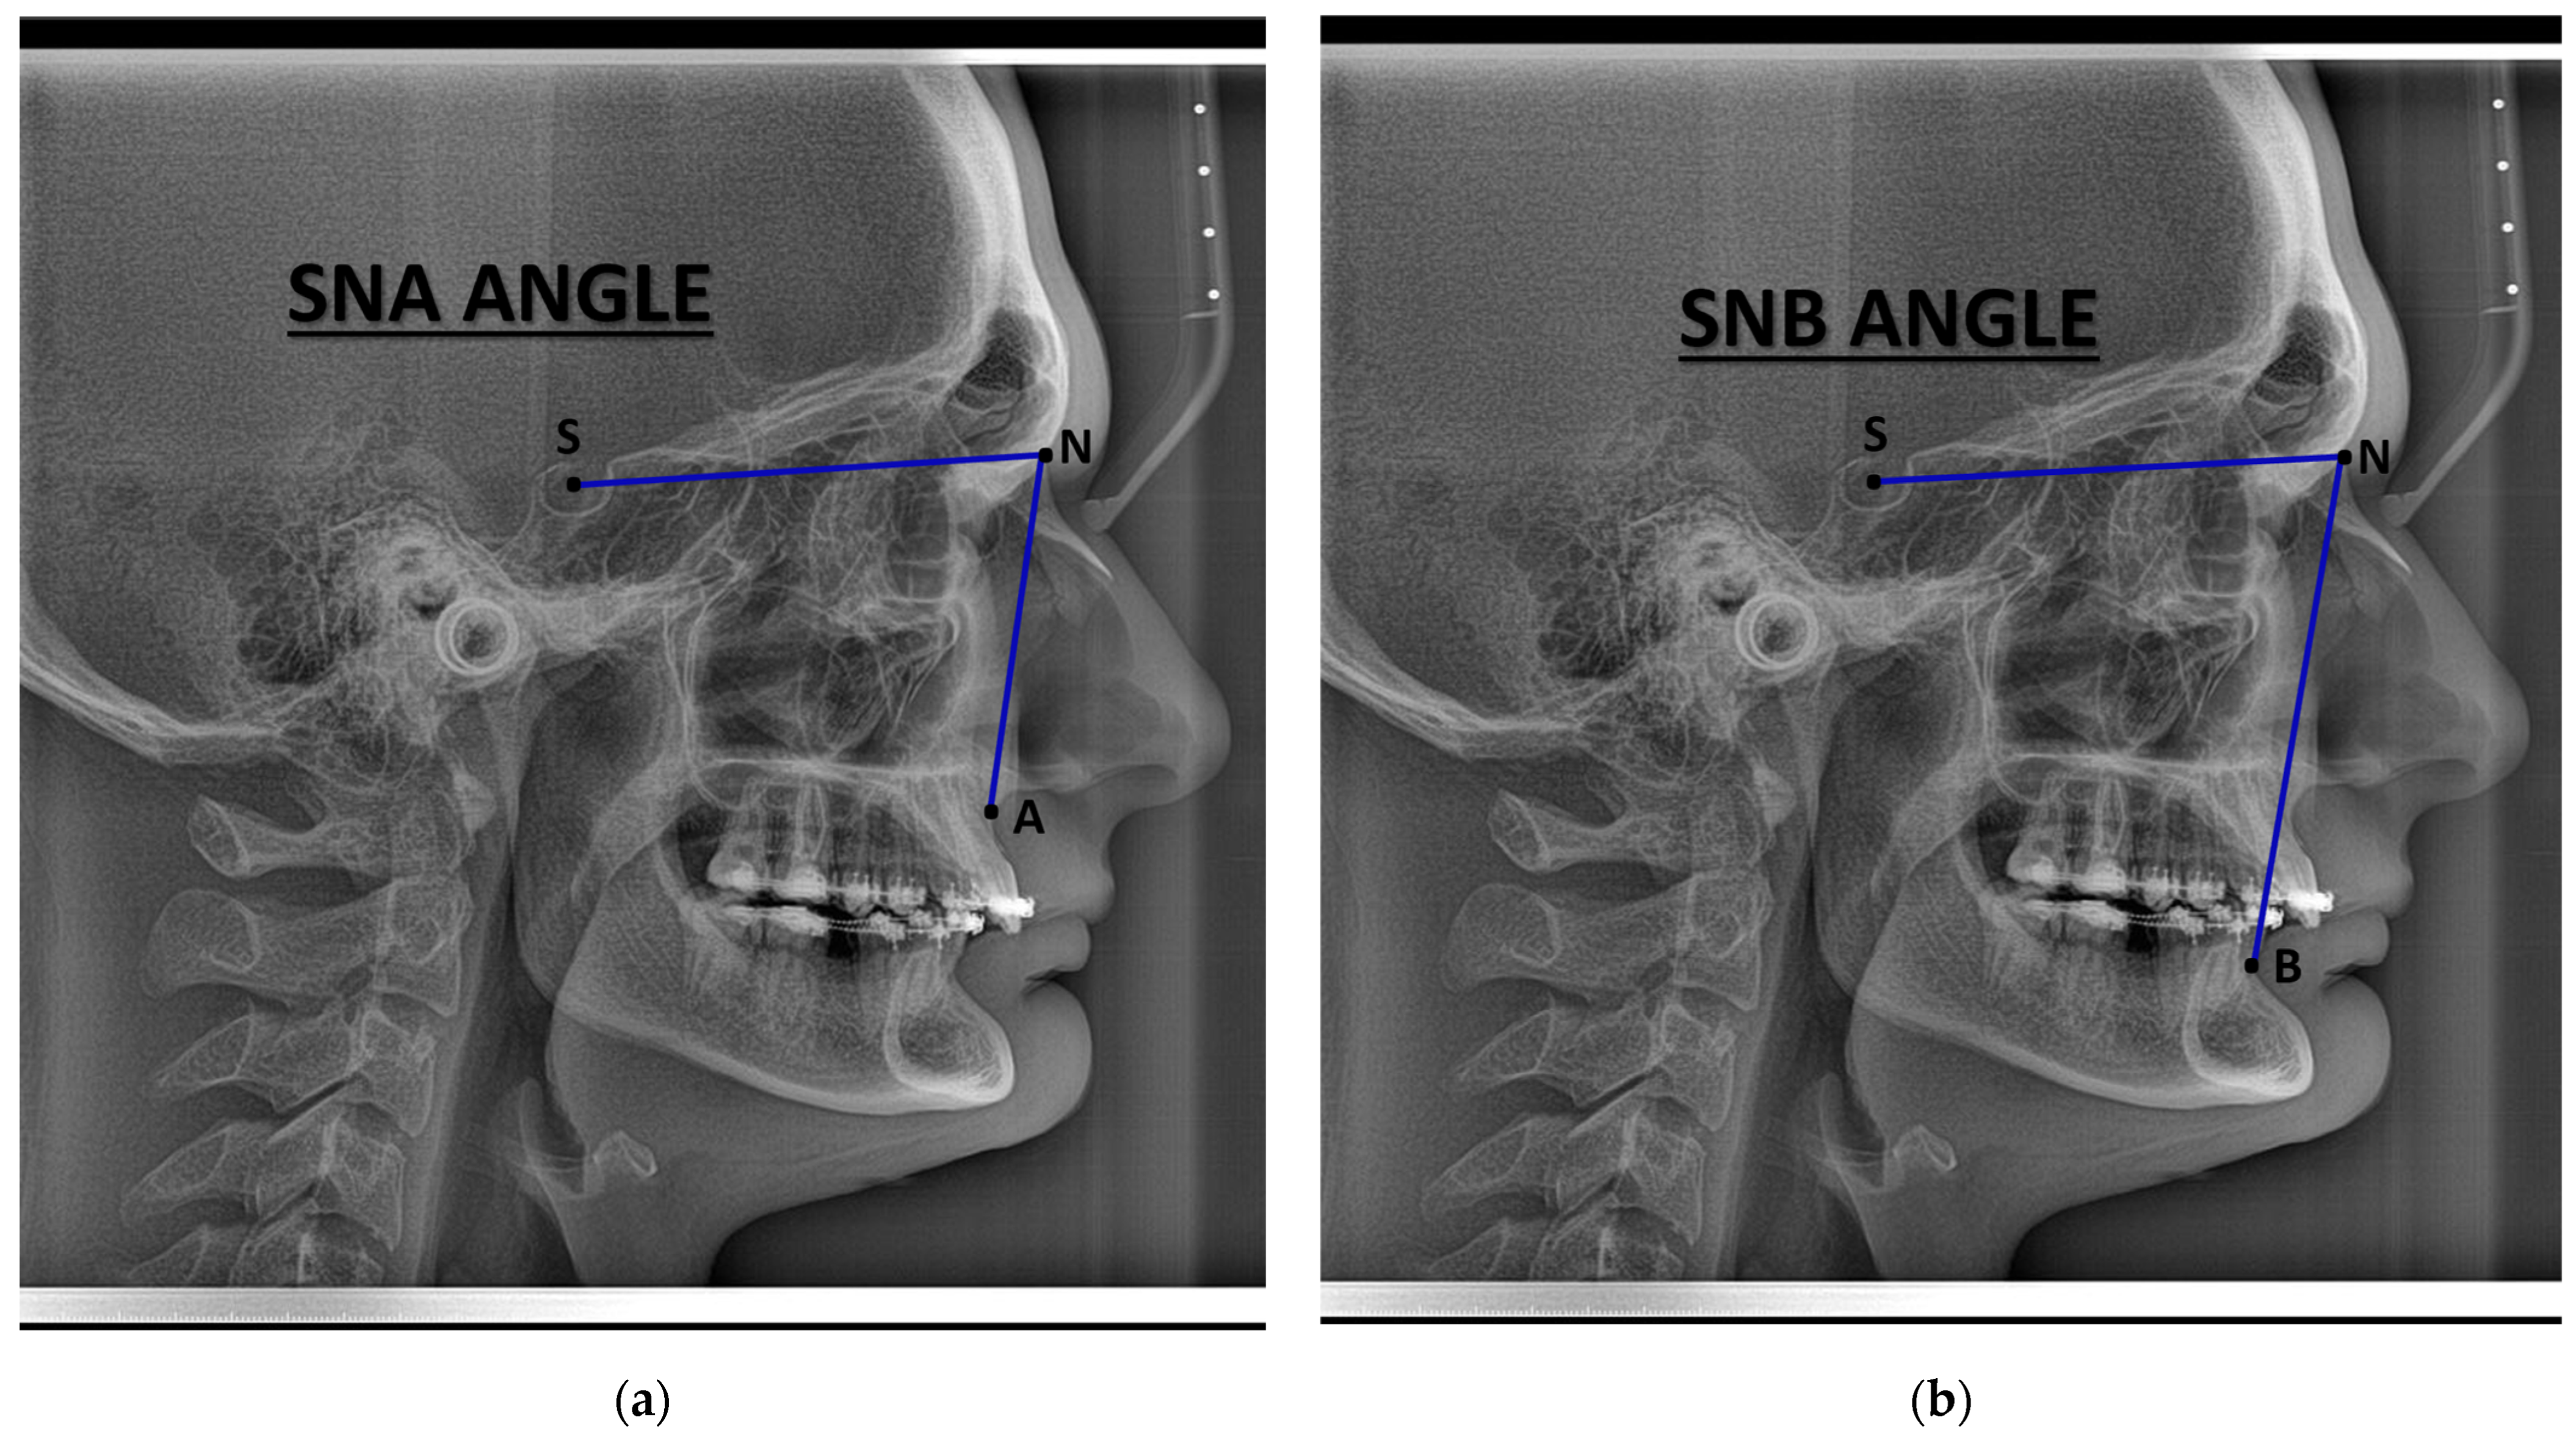

| SNA (°) | 83.6 (79.9, 84.9) | 86.3 (80.4, 89.0) |

| SNB (°) | 83.5 (76.8, 87.2) | 84.0 (81.0, 86.0) |

| SNA (°) | −3.123 | 1.24 | −2.511 | 24 | 0.019 |

| SNB (°) | −1.147 | 1.41 | −0.811 | 24 | 0.426 |